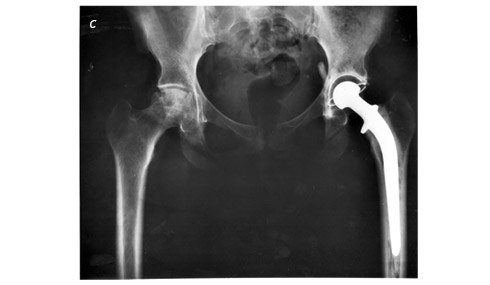

Другой проблемой, стоявшей перед Джоном Чарнли, были бактериальные инфекции. Вживление крупных металлических и полиэтиленовых деталей требовало больших разрезов и влекло за собой значительный риск инфицирования раны. В случае заражения приходилось удалять элементы протеза, и пациент чувствовал себя так, словно ему просто срезали головку бедренной кости. Бактерии обязательно присутствуют в воздухе операционной и с большой долей вероятности могут попасть в рану – напрямую или через хирургические инструменты. Чарнли начал наступление по трем направлениям. Он разработал «скафандры» для всей хирургической бригады. Костюмы имели систему вентиляции, поэтому людям в них было комфортно даже несмотря на то, что эти «скафандры» закрывали их с головы до ног. Также Чарнли усовершенствовал вентиляционную систему операционной: для очистки поступавшего воздуха от большинства бактерий и пыли установили высокоэффективные фильтры. Кроме того, отфильтрованный воздух направляли ламинарным потоком – так, чтобы самый чистый слой оказывался рядом с хирургическим разрезом. ![]() ![]() Сэр Джон Чарнли в перерыве между операциями поднял шлем «скафандра», которым он пользовался для предотвращения заражения (a). Протез тазобедренного сустава состоит из полиэтиленовой чаши, которая крепится к тазовой кости, и металлического шара со стержнем, который вставляют в бедренную кость (b). На рентгеновском снимке показано расположение новых элементов тазобедренного сустава и проволочный маркер вокруг ячейки сустава. Изображенный протез – один из многих вариантов, созданных на основе успешного проекта Джона Чарнли (c) Национальная медицинская библиотека США (a); Tom Schmalzried, MD (b); Национальный институт диабета, расстройств пищеварения и заболеваний почек, США (c) К концу 1960-х годов Джон Чарнли разобрался со всеми этими сложностями, и эндопротезирование тазобедренного сустава стало будничной и безопасной процедурой. К Чарнли потянулись хирурги-ортопеды со всего мира. Он настаивал, чтобы перед возвращением домой с набором инструментов доктора проходили специальный курс. Этот курс длился два с половиной дня и включал не только изучение хирургических методик – врач должен был уметь воспроизвести результаты, – но и тщательное ведение записей для последующего анализа. Состав и форма протезов, а также методы хирургического вмешательства продолжают совершенствоваться. В США ежегодно проводится около 300 тысяч операций по замене тазобедренного сустава: через эту процедуру прошло около одного процента населения страны. По влиянию на качество жизни артропластику сравнивают с лекарственной терапией артериальной гипертензии, диализом при хронической почечной недостаточности, стентированием и шунтированием при ишемической болезни сердца. Дело Джона Чарнли продолжили другие ортопеды. Они разработали прекрасные протезы для пораженных артрозом коленных и плечевых суставов. Тяжелый артроз и болезненность крупного сустава напоминают о себе при каждом движении и делают инвалидом здорового в целом человека. Вот почему мы с уверенностью можем сказать, что Джон Чарнли внес неоценимый вклад в современную медицину. Как вы помните, за это ему было пожаловано рыцарское звание. Сэр Джон получил славу и признание уже при жизни. Другим первопроходцам повезло меньше. Так бывает не только в ортопедии. Современники часто игнорируют, принижают нестандартно мыслящих людей и пренебрежительно к ним относятся. Галилея посадили под домашний арест за утверждение, что Земля не является центром Вселенной. Лично я не встречал ни одного ортопеда-новатора, посаженного под домашний арест. Однако я познакомлю вас с несколькими историями, когда путь к славе и триумфу оказывался крутым и тернистым, а случалось, что успех так и не приходил. ![]() Внешняя рама, закрепленная с помощью велосипедных спиц вокруг тяжело травмированной кости, произвела революцию в лечении осложненных переломов, не поддававшихся традиционной терапии (a). Изобретатель Г. А. Илизаров (слева) вместе со своим знаменитым пациентом, олимпийским чемпионом по прыжкам в высоту В. Н. Брумелем. На правой ноге спортсмена – аппарат Илизарова (b) Svetlana Ilizarov, MD (b) Герой первой истории – российский врач Гавриил Абрамович Илизаров. Он родился в Польше, учился в Крымском медицинском институте, во время Великой Отечественной войны вместе с институтом был эвакуирован в Казахстан. Не имея никакого практического опыта, Илизаров начал работать врачом в Курганской области – это почти две тысячи километров к востоку от Москвы, далеко от авторитетных центров медицинской науки. Война не обошла и этот регион стороной: туда прибывало много раненых, которые страдали от плохо заживавших, инфицированных переломов. Стремление помочь раненым, недостаток ресурсов и отсутствие предрассудков натолкнули Илизарова на мысль разработать наружную раму, которая фиксировала бы большеберцовую или бедренную кость на время заживления. Он поместил спицы перпендикулярно кости с обеих сторон перелома так, как это уже делали до него. Спицы выходили через кожу и крепились к металлическим кольцам вокруг конечности: чуть выше и чуть ниже места повреждения. Затем Илизаров дополнил свою конструкцию, стянув кольца продольными металлическими штифтами. Его устройство отличалось от применявшихся ранее тем, что штифты имели резьбу. В 1955 году Илизаров стал заведующим ортопедо-травматологическим отделением в своем сибирском форпосте. Дефицит ресурсов требовал импровизации, поэтому Илизаров использовал в работе велосипедные спицы и сравнивал получившуюся конструкцию с велосипедным колесом: концы кости, как втулки, полностью стабилизированы идущими от них к ободу спицами. Устройство исключало какое-либо движение между зафиксированными концами кости, благодаря чему остеобласты наконец получали возможность заживить перелом. Оставалась еще одна проблема – сократить промежуток между обломками кости: у «прыгучести» остеобластов есть свои пределы, и целый каньон они не преодолеют. Чтобы уменьшить расстояние, Илизаров решил понемногу сдвигать фрагменты кости и начал ежедневно корректировать положение колец на резьбовых стержнях. Лечение занимало не одну неделю, и доктор показывал пациентам с осложненными переломами, как выполнять эту манипуляцию в домашних условиях. Какой-то пациент все перепутал и упорно поворачивал винт в противоположном направлении, постепенно расширяя, а не уменьшая промежуток между фрагментами кости. К изумлению Илизарова, несмотря на то что пробел увеличивался, кость заполнила его и зажила обычным образом. Остеобласты – эти микроскопические труженики – усердно вырабатывали коллаген и гидроксиапатит, не подозревая, что их задача усложняется. Наружное растяжение применялось для удлинения конечностей и раньше, но хирурги заполняли промежуток между фрагментами костей трансплантатом, взятым из другого места организма пациента. Для этого требовалось дополнительное хирургическое вмешательство, сопряженное с риском болей, обезображивания и инвалидности. Илизарова осенило. Он понял, что очень медленное (шесть корректировок в день, меньше полутора миллиметров) расширение промежутка между отломками кости позволит новой костной ткани заполнить пробел. (Дерни лакричную палочку – она порвется. Потяни медленно, и она растянется.) Более того, Илизаров обнаружил, что таким образом можно выправить кость, зажившую с любыми искривлениями, поворотами и сокращением длины. (Поворачивай и сгибай лакричную палочку, и она поддастся.) |